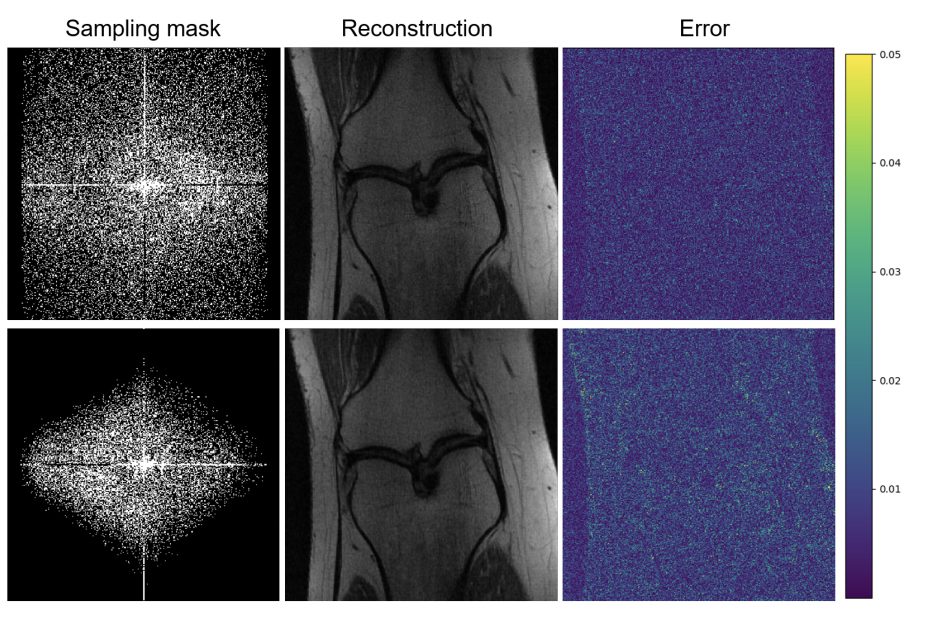

Gopal Nataraj receives ISA Fellowship to support research that will improve MRIs

Nataraj’s research aims to generate higher-quality and faster MRI images, resulting in improved diagnostics of neurological disorders and autoimmune diseases.

Gopal Nataraj earns Best Paper Award for improving MRI

Nataraj is using big data techniques to transform the field of medical imaging

Student Spotlight: Mai Le – Finding a better way to diagnose breast cancer with MRI

The research group is using statistical signal processing to create crisper images with only 20% of the data required by a traditional MRI scan.

Hao Sun earns 3 Paper Awards for medical imaging research

Hao’s research is focused on improving the quality of images from magnetic resonance imaging pulse design.

Three teams of graduate students awarded prizes for their final projects in Image Processing (EECS 556)

KLA sponsored prizes for three outstanding projects focused on improving image processing for neurosurgery and satellite applications and MRI reconstruction techniques.